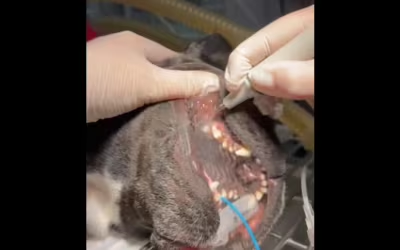

Problemy z zapaleniem dziąseł oraz przyzębia

Nasz pacjent cierpiał na przewlekłe, nawracające problemy z zapaleniem dziąseł oraz przyzębia. To niestety bardzo częsty problem nawet u młodych kotów.